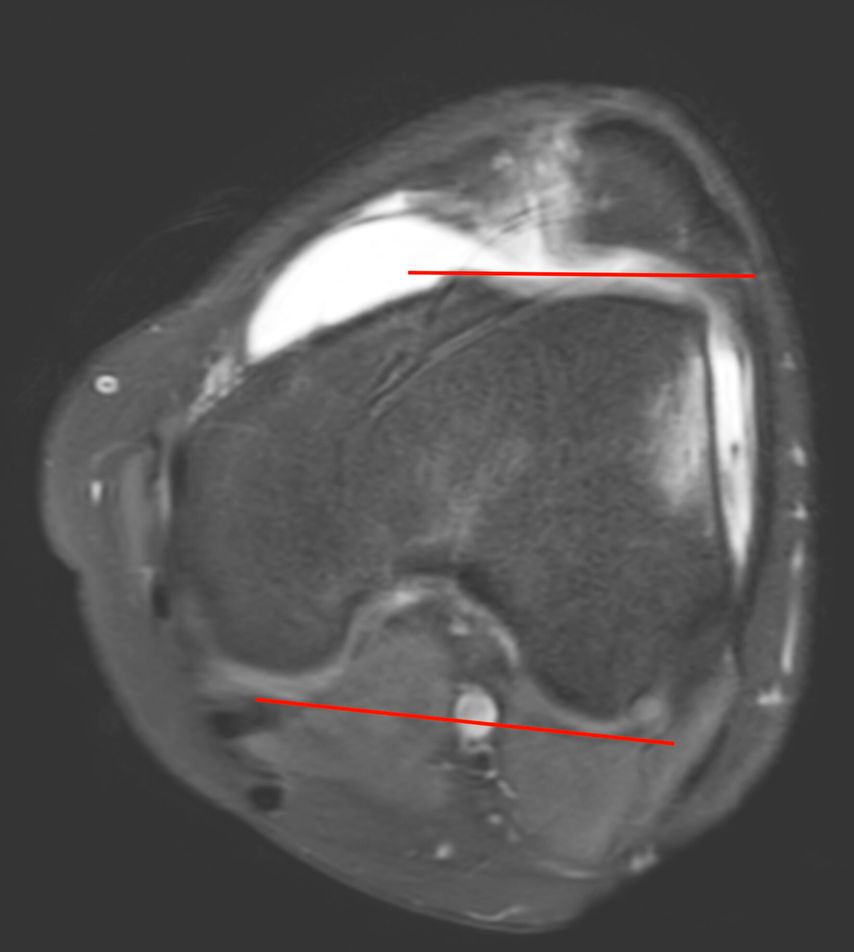

Eine Instabilität bis circa 30° ohne weitere Auffälligkeiten in der radiologischen Untersuchung wird mittels alleiniger MPFL-Rekonstruktion stabil. Ab circa 0–60° Instabilität gibt es zumeist Probleme mit der knöchernen Führung. Dies kann aufgrund eines zu späten Eingleitens der Patella – einer Patella alta – und/oder des Fehlens einer knöchernen Führung (Trochleadysplasie) auftreten. Unserer Meinung nach bedarf es einer Korrektur der Patella alta ab einem Caton-Deschamp-Index >1,2 (Abb.1) und/oder einer LTI (laterale Trochleainklination) von <17° (Abb. 2). Ab 60° ist zusätzlich ein Problem im Bereich des Alignments wahrscheinlich. Bei einer vermehrten Innenrotation des Femurs und der Tibia bei ca. 35° und/oder valgischer Beinachse ab ca. 5° wird eine Korrektur in Erwägung gezogen (Abb.3). Prinzipiell sind wir bei einer Alignmentkorrektur eher zurückhaltend (von manchen Autoren wird bereits eine Korrektur ab 20° Innenrotation empfohlen).5 Ein vermehrter TTPCL-Abstand (lateraler Kraftvektor der Patella) ab circa 24mm kann die Luxation ebenfalls begünstigen und bei einer Patella alta mitkorrigiert werden. Sollte eine knöcherne Stabilisierung notwendig sein, ist bei der Trochleaplastik eine arthroskopische oder offene Technik möglich.